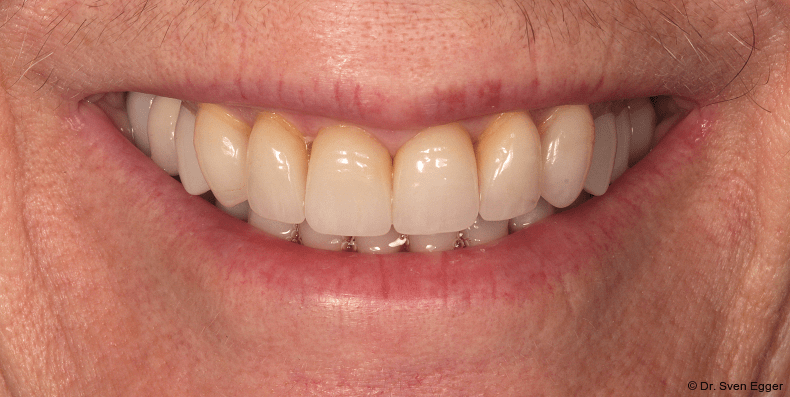

- Zahnlänge: Die Verlängerung der gesamten Oberkieferfront um ca. 1 mm empfindet die Patientin als sehr attraktiv, das entspannte Lächeln zeigt fast die gesamte Frontzahnreihe. Der Schneidekantenverlauf folgt der Konkavität der Unterlippe.

- Zahnform: Die größeren und längeren Schneide- und Eckzähne sowie die kleine Stellungskorrektur der beiden seitlichen Schneidezähne fügen sich harmonisch in das Gesamtbild der Restbezahnung ein und schenken der Patientin ein attraktives Erscheinungsbild (Abb. 15).

- Form und Größe, Charakterisierung durch den ausführenden Zahntechniker (Transparenz, Transluzenz) sowie die Oberflächenstruktur (Textur) der keramischen Veneers zeigen ein ansprechendes Erscheinungsbild. Das Längen-Breiten-Verhältnis beträgt nun circa 80 Prozent (Länge 11 mm, Breite 8 mm).

- Zahnstellung: Die leicht nach distal rotierten seitlichen Schneidezähne konnten durch die Einzelzahnrestaurationen etwas ausgeglichen werden. Durch die „Verlängerung“ der Eckzähne konnte gezielt eine gute Front-Eckzahn-Führung in die Veneerrestaurationen eingearbeitet werden.

- Zahnfarbe: Die Zahnfarbe entpricht ganz den Vorstellungen der Patientin (A2, VITA).

Zusammenfassung der ästhetischen Problematik: Es zeigt sich nun hinsichtlich der Länge (Lächeln), Form, Farbe, Stellung der Zähne sowie der rosa Ästhetik ein ansprechendes dentogingivales Erscheinungsbild. Die unteren Frontzähne haben leichten Kontakt auf den Palatinalflächen der oberen Eck- und Schneidezähne. Der Overbite beträgt 4 mm. Der Overjet 2 mm (Abb. 16+17).